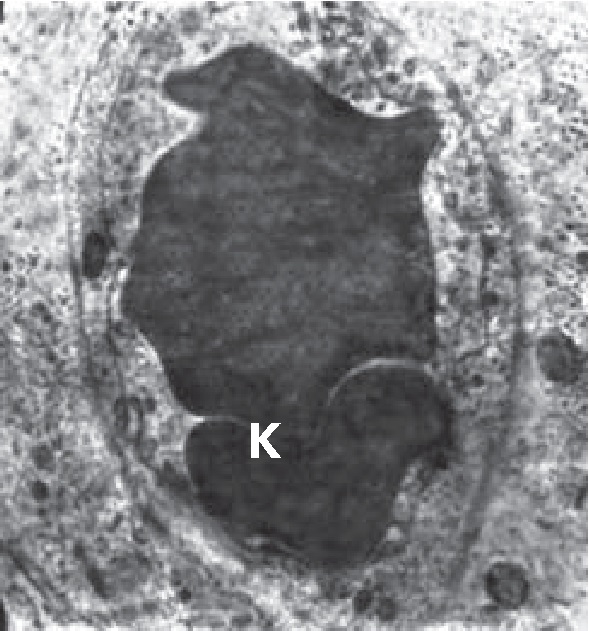

Тело ПЖ при начальной фазе ОДП хорошо васкуляризировано, однако стенки капилляров изменены, и в их просвете в ряде случаев наблюдается капилляростаз (рис. 3). Вблизи некоторых сосудов часто встречаются сильно вакуолизированные клетки с распадающимися гранулами и отдельные очень крупные вакуоли с почти прозрачным содержимым.

Рис. 3. Капилляростаз капилляров тела ПЖ. Капилляр (К)заполненный эритроцитами, ув. ×10000